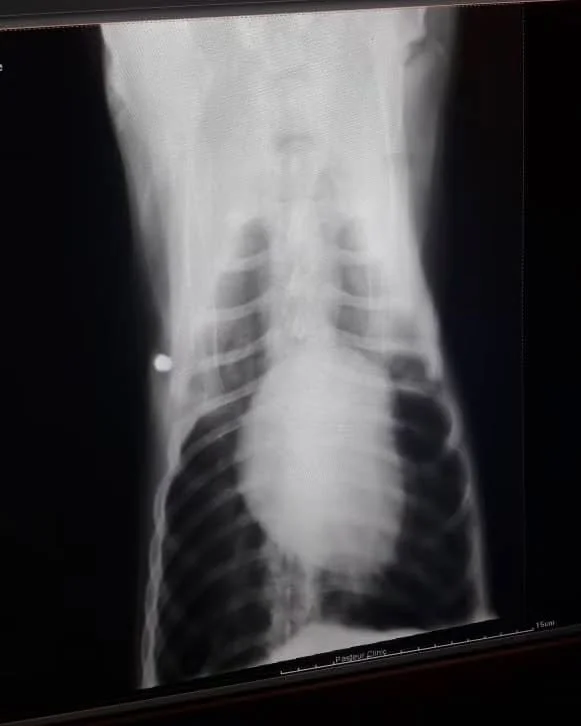

Once his trembling eased, the shelter team rushed him to the veterinarian. X-rays revealed the truth: multiple shotgun pellets lodged dangerously close to his spine. Each one was a cruel reminder of what he had endured, each one a risk to his fragile body.

And this was not the only case. The dog filled with shotgun pellets is one of many we have seen. Again and again, animals arrive at the shelter carrying the scars of deliberate shootings, their bodies riddled with metal fragments. The images and videos that follow are not isolated tragedies — they are part of a larger pattern of cruelty. Each survivor requires surgery, medication, and months of care, and each one deserves the chance to heal.